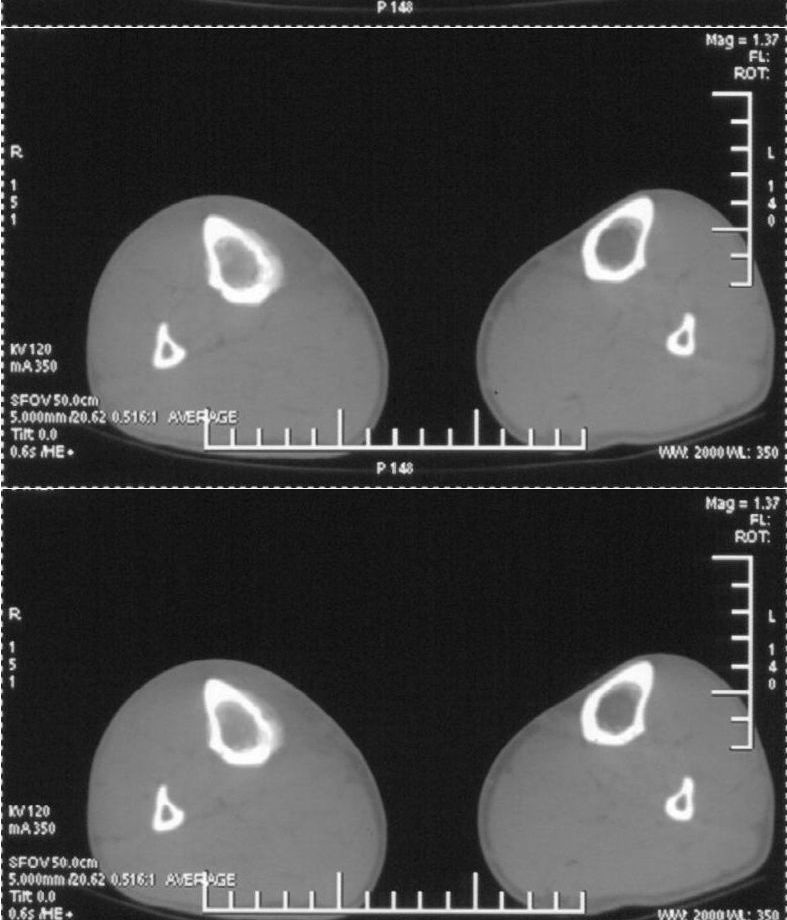

男,42岁。4个月前钢筋钝伤右侧小腿部,当时因无明显外伤,未引起重视。一周后因受伤腿部疼痛,发现肿胀,随后到当地医院进行检查(2008年4月16日)。因未发现骨质异常未引起重视,仅仅进行口服抗生素治疗处理。经过一段时间治疗但未见明显治疗效果在5月29日又进行x线检查,发现有胫骨密度上段密度增高,又进行抗炎治疗,仍未见效果。又在7月3日进行x线检查,仍然报告有胫骨上端密度增高,并建议ct检查。以下是相关检查结果:

髓腔密度呈絮状增高,胫骨上端内侧可见层状骨膜反应,考虑骨髓炎.

髓腔密度呈絮状增高,胫骨上端内侧可见层状骨膜反应,肌间隙模糊,考虑骨髓炎.